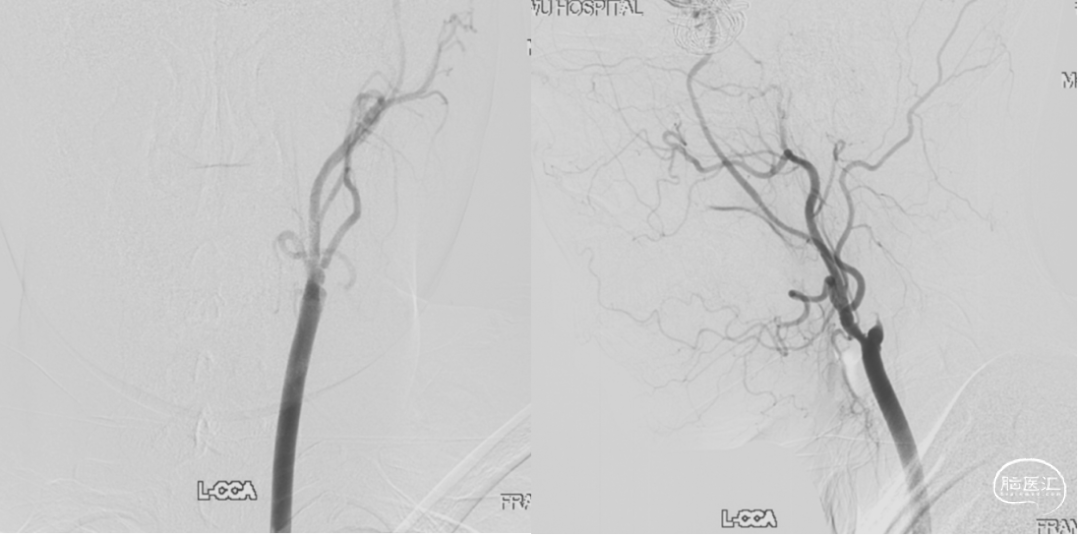

颈内动脉狭窄状况及闭塞试验

1. 术后一周复查DSA显示动脉瘤无血流,桥血管通畅。